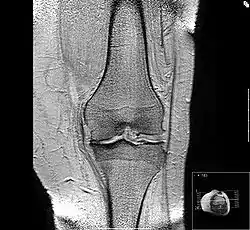

رنين مغناطيسي علي الركبة يوضح هشاشة عظام وضيق في المسافة الداخلية للمفصل.

هشاشة العظام الابتدائية في الركبة اليسرى. يلاحظ وجود عظيمات، وضييق المساحة داخل المفصل (السهم)، وزيادة كثافة العظام تحت الغضروف (السهم).